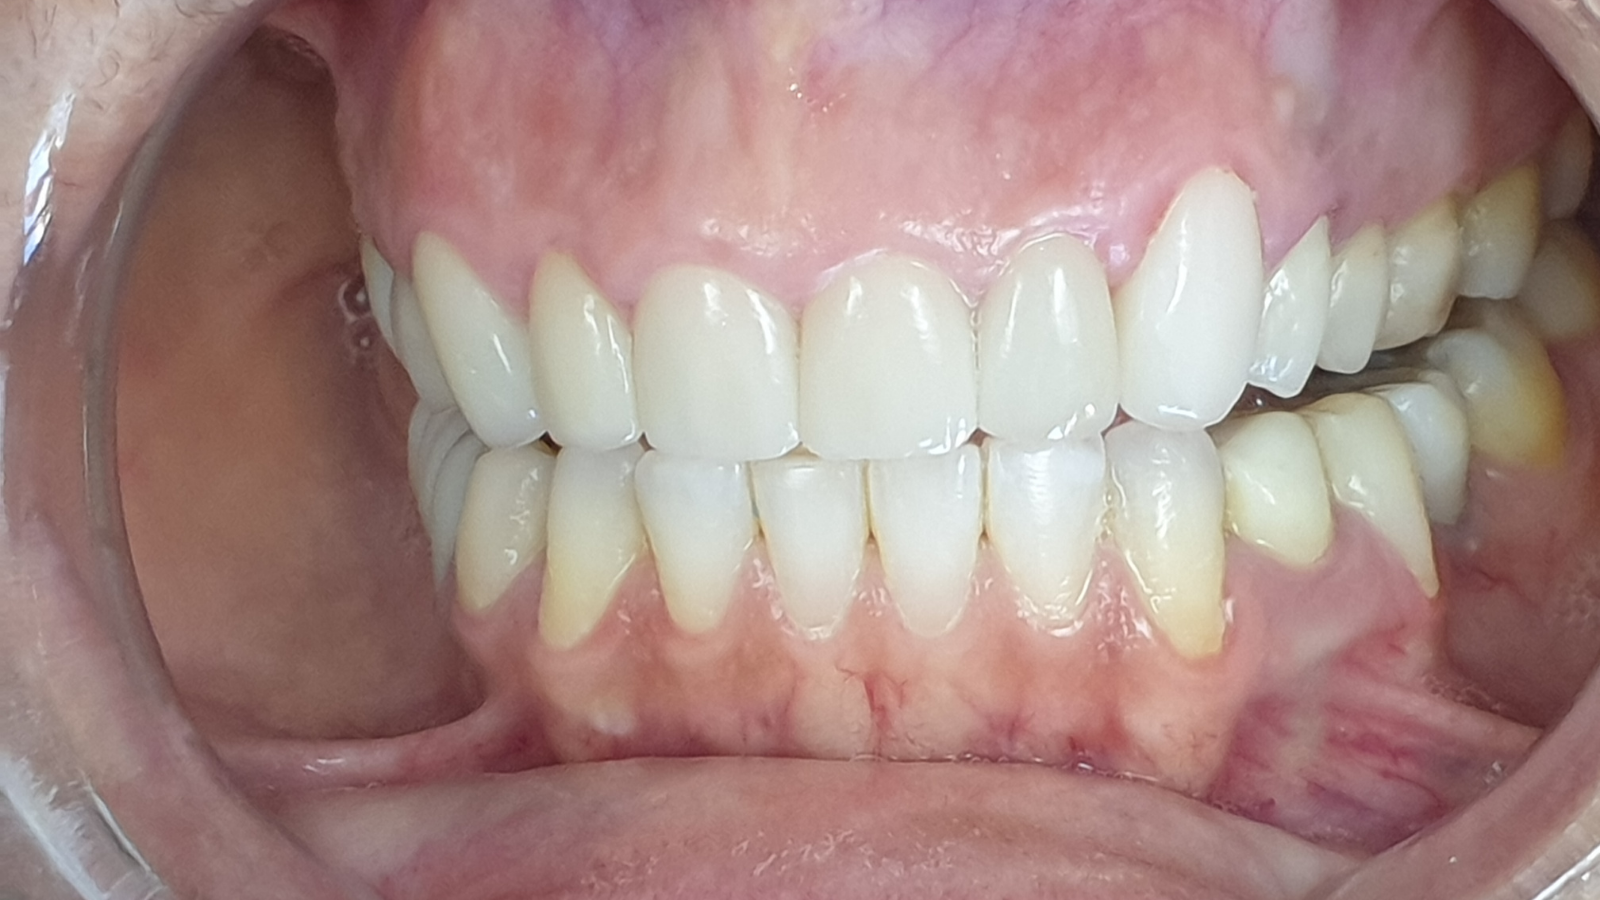

Réhabilitation esthétique après orthodontie : full-zircone & disilicate de lithium

Une jeune patiente arrive en fin de traitement orthodontique pour un déficit esthétique.

La difficulté réside dans la réalisation de prothèses différentes dans le même secteur : jongler avec la full-zircone et le disilicate de lithium.

Ce challenge fut le sujet de mon mémoire du DU d’esthétique de Strasbourg en 2008.

L’expérience et l’investissement dans le digital depuis 2017 rendent le résultat plus prévisible.